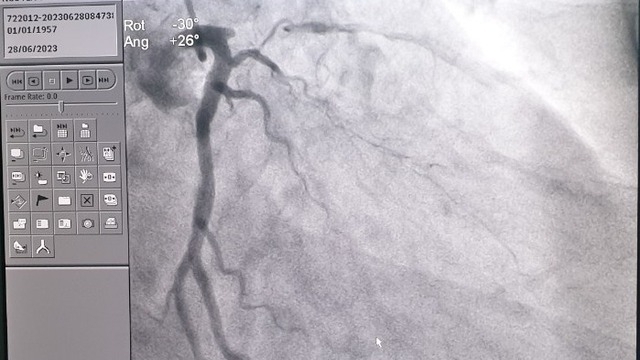

PGS.TS Phạm Duy Hiền - Phó Giám đốc Bệnh viện, Trưởng khoa Ngoại tổng hợp, Bệnh viện Nhi Trung ương cho biết, trở ngại lớn nhất mà các bác sĩ phải vượt qua trong ca ghép này là trường hợp ghép gan cho trẻ em đầu tiên trên nền một bệnh lý ác tính, nhiều nguy cơ biến chứng và rủi ro rất cao. Chính vì điều này, việc tầm soát các tổn thương xâm lấn sang các cơ quan khác là vô cùng quan trọng trước khi tiến hành thay thế gan bằng mảnh ghép gan mới. Các xét nghiệm tầm soát di căn trước phẫu thuật đã được tiến hành một cách thận trọng và tỉ mỉ nhằm đưa ra các phương án phẫu thuật tối ưu.

Tình trạng khối u quá lớn, chiếm toàn bộ thể tích gan, đặc biệt có một phần u xâm lấn và chèn ép tĩnh mạch chủ . Thêm vào đó, tình trạng bất đồng nhóm máu hệ ABO giữa người cho và người nhận (cháu bé có nhóm máu O trong khi người mẹ có nhóm máu B) cũng là một khó khăn rất lớn về chuyên môn trong ca ghép.

Theo Đại tá TS. Lê Văn Thành = Chủ nhiệm Khoa Phẫu thuật Gan-Mật-Tụy, Bệnh viện Trung ương Quân đội 108: “Trước phẫu thuật, chúng tôi đánh giá bệnh nhi có khối u lớn, có khả năng xâm lấn vào tĩnh mạch chủ, vì vậy việc phẫu thuật sẽ gặp khó khăn, chúng tôi đưa ra phương án có thể phải thay cả đoạn tĩnh mạch chủ dưới cho bệnh nhi.

Trong ca mổ, nhờ việc phẫu tích chính xác và xử lý tốt các mạch máu, chúng tôi không phải sử dụng phương án thay thế đoạn tĩnh mạch chủ dưới. Với sự quan tâm, chỉ đạo và sự phối hợp, hiệp đồng chặt chẽ giữa hai bệnh viện, tận dụng những kinh nghiệm trong ghép gan, gây mê hồi sức, tổ chức điều phối… ca phẫu thuật được thực hiện thành công”.